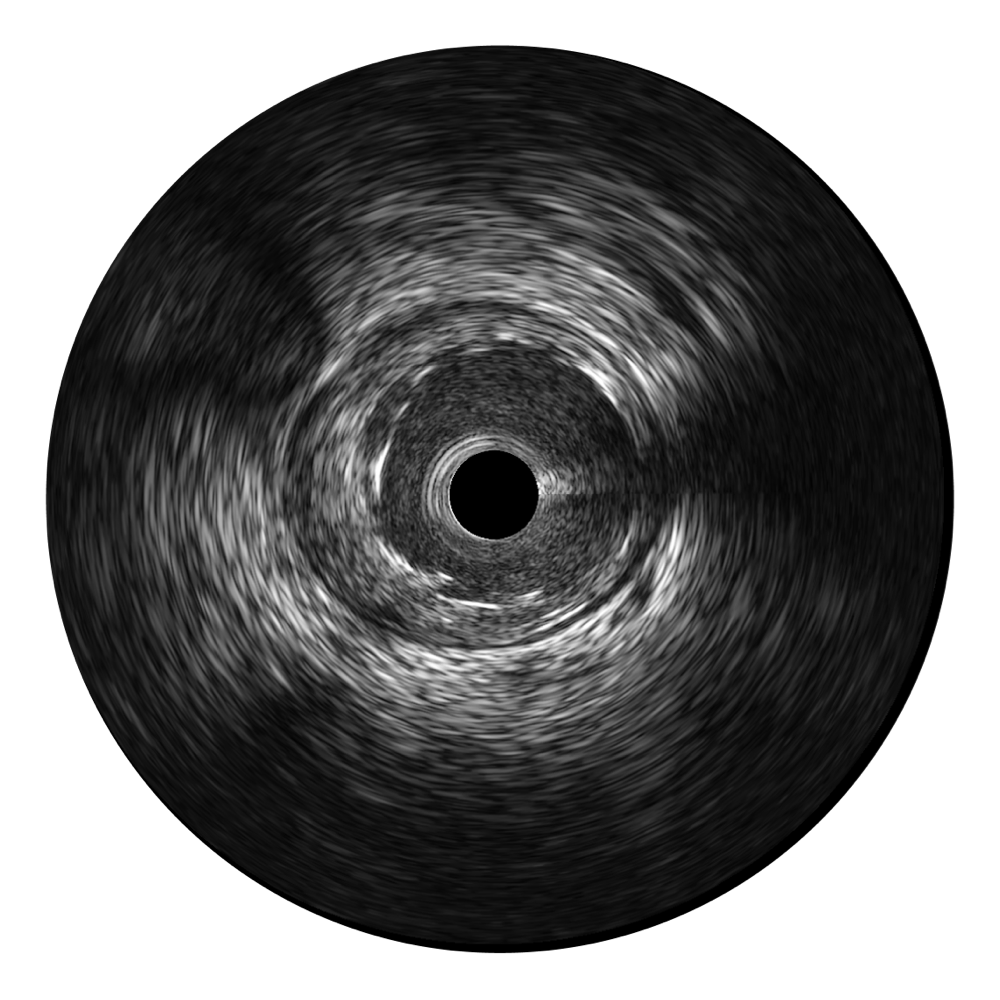

环球UG官网宽频IVUS图像

对比传统IVUS导管成像,环球UG官网宽频IVUS图像的近场支架梁显影更细腻,远场中膜外血管仍清晰可辨,兼顾远中近,兼顾分辨力与穿透深度